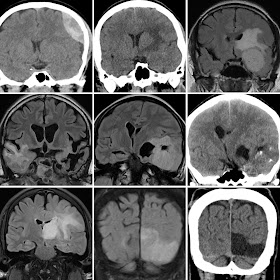

Typical examples or real-life scenarios can be used to illustrate theory, and help students understand fundamental principles. Mastering a topic usually requires exposure to and experience with many examples, both typical and atypical, common to uncommon including subtle manifestations of a phenomenon. The traditional method of doing this is via a long apprenticeship, or many years of practice with feedback and experience. A digital collection of educational scenarios and cases can support and potentially shorten this educational and training process. Particularly if a systematic attempt is made to collect and curate a comprehensive collection of all possible educational scenarios and case-based examples, across the whole spectrum of professional practice. Online access to key elements, parts of and whole sections of these learning cases; used by students with guidance by instructors under a deliberate practice and mastery training framework, can potentially accelerate the educational process, and deepen learning."